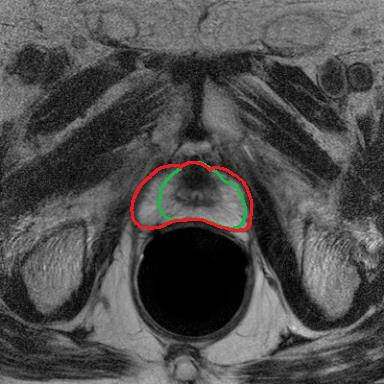

Modern deep neural networks struggle to transfer knowledge and generalize across diverse domains when deployed to real-world applications. Currently, domain generalization (DG) is introduced to learn a universal representation from multiple domains to improve the network generalization ability on unseen domains. However, previous DG methods only focus on the data-level consistency scheme without considering the synergistic regularization among different consistency schemes. In this paper, we present a novel Hierarchical Consistency framework for Domain Generalization (HCDG) by integrating Extrinsic Consistency and Intrinsic Consistency synergistically. Particularly, for the Extrinsic Consistency, we leverage the knowledge across multiple source domains to enforce data-level consistency. To better enhance such consistency, we design a novel Amplitude Gaussian-mixing strategy into Fourier-based data augmentation called DomainUp. For the Intrinsic Consistency, we perform task-level consistency for the same instance under the dual-task scenario. We evaluate the proposed HCDG framework on two medical image segmentation tasks, i.e., optic cup/disc segmentation on fundus images and prostate MRI segmentation. Extensive experimental results manifest the effectiveness and versatility of our HCDG framework.